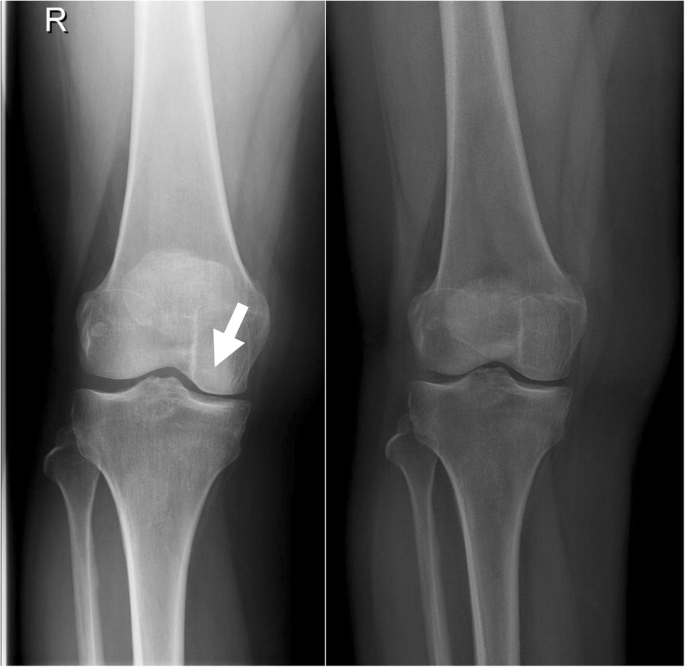

Whatsapp x WhatsApp Number Message phone x email x info@imagesradiologycom If you know, EOS is a low dose weight bearing XRay technology Images of the human body or the skeletal system can be produced in 2D or 3D form Contact us Home;The EOS Imaging System is a revolutionary advance in xray imaging Using Nobel Prizewinning technology, the ultralowdose system scans our patients in an upright, weightbearing position in seconds This allows the doctor to see the natural way that their joints interact with their musculoskeletal system, making it ideal for diagnosing

The new EOS Xray system uses significantly lower radiation in the diagnosis of scoliosis Patients stand or sit inside the imaging system while it takes spAbstract Background EOS is a biplane Xray imaging system manufactured by EOS Imaging (formerly Biospace Med, Paris, France) It uses slotscanning technology to produce a highquality image with less irradiation than standard imaging techniques Objective To determine the clinical effectiveness and costeffectiveness of EOS twodimensional (2D)/threedimensional (3D) X The EOS™ Xray machine, based on a Nobel prizewinning invention in physics in the field of particle detection, is capable of a simultaneous capture of biplanar Xray images by slot scanning of the whole body in an upright, physiological loadbearing position, using ultralow radiation doses

EOS is highly efficient as this imaging system uses low does of radiation compared to the other MRIs It can give the physicians a better hand to preplan the treatment for the children which can bring out effective results An EOS scan can effectively show the child’s natural weight bearing posture and even allows us to see the interaction between joints and hips, spine and legs EOS Xrays produce highquality detailed images and expose patients to significantly lower doses of radiation than traditional Xrays “An EOS imaging system is important for kids with scoliosis because the radiation dose is about 1/7th of a normal Xray dose at the initial visit and much lower still for followup Xrays using the microdoseNo evidence was found on the impact of EOS on patients' pathways of care or ultimate health outcomes Radiation dose is considerably lower with EOS than CR or film Xray imaging, whereas image quality remains comparable or better with EOS Patient throughput is the major determinant of the costeffectiveness of EOS